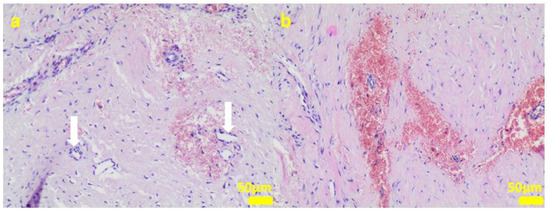

2.1. In Vitro Examinations

4.3. Cell Cultures